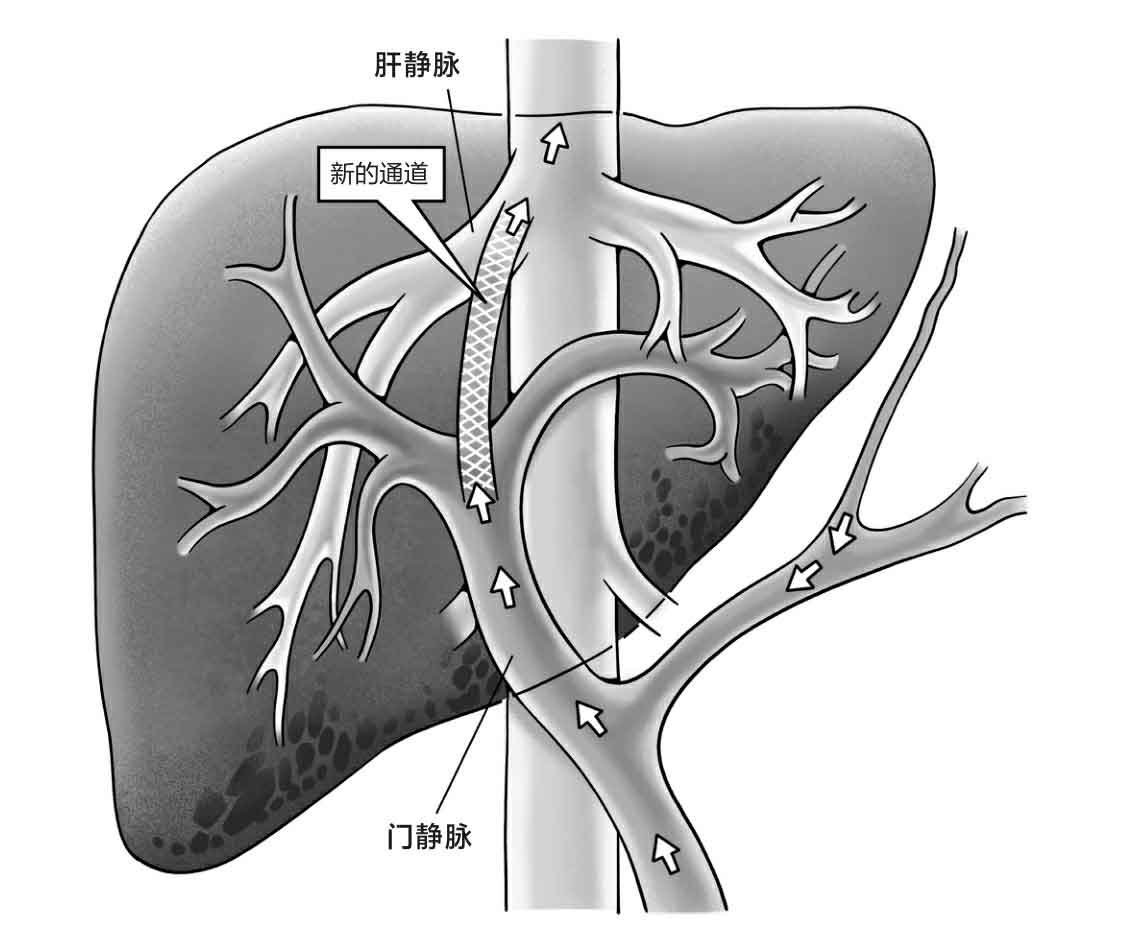

而给肝硬化、上消化道大出血患者做介入手术止血很像人类的治水:当一条河道决堤引起洪涝时,不仅要堵,更要疏。换句话说,王大夫不仅要把出血的血管栓塞住,这是“堵”,更关键的是,他要在高压的门静脉和低压的肝静脉之间打出一条新通道,这是“疏”,让门静脉里的一部分血流向肝静脉,这叫“分流”。

这种手术的医学名称叫经颈静脉肝内门体分流术(Transjugular Intrahepatic Portosystemic Shunt),简称TIPS。世界各地权威指南都指出,对于经内科药物治疗和内镜治疗失败的急性出血,TIPS可以作为挽救治疗措施[中国医师协会介入医师分会. 中国门静脉高压经颈静脉肝内门体分流术临床实践指南(2019年版)[J]. 临床肝胆病杂志,2019,35(12):2694-2699.]。TIPS治疗对肝硬化、门静脉高压引起的上消化道出血的控制率高达90%~100%。

接下来,就到了整台手术最核心也最困难的步骤了。王大夫要在高压的、引起患者大出血的门静脉和另外一条压力相对低的静脉——肝静脉之间,凭空打出来一条新通道,让门静脉里的血通过这条新通道流向肝静脉,这么做就像“泄洪”。“泄洪”后,门静脉内压力降低,就可以防止上游的胃部、食管的静脉再出血了。

在门静脉和肝静脉这两条血管之间本来是没有自然通路的,医生要先刺破肝静脉的血管壁,然后让穿刺针一路穿过肝脏组织,再穿透门静脉的血管壁,建立一条新通路。这其实就像把开拓运河、打通隧道这两种地球上最伟大的建筑技术运用到人体内,医生完全在X射线的辅助下,用穿刺针穿透肝脏(打隧道)打出一条新的血流通道(挖运河),让这条新通道把两条已有的血管连接起来。TIPS

手术示意图

其次是盲穿。“盲”这个字意味着术者看不见这个打通道的过程,如何操作全凭个人经验。在临床上,任何手术只要术者能通过肉眼或者通过设备看见手术部位,再难都有办法克服,但TIPS手术之难在于医生完全是在看不见的情况下,根据两条血管的空间关系,凭借个人经验,定好穿刺位置、角度后进针穿刺。穿刺要经过肝脏组织,不同肝硬化患者的病因不同,其肝脏组织密度和肝脏体积也不相同,所以穿刺过程中还要不停地调整穿刺角度。

除了从无到有和盲穿,TIPS手术之难还在于非标准化。如果是标准化的手术,医生根据指南操作,通过标准化的器械、路径来做,大概率可以保障手术效果和手术的安全性。但TIPS手术全凭医生个人经验和患者独特的个体情况来打一条新通路。

这个通路应该打多粗?如果内径太粗,血流流速快,门静脉压力瞬间降低,止血效果肯定好,但代价是门静脉压力大幅度下降,门静脉流向肝脏的血流快速减少,接下来患者的肝脏可能会因为血供不足而发生肝功能衰竭,严重肝衰竭会加速患者死亡;但反过来,如果这条新通路打得过细,门静脉压力下降不理想,术后患者还会再次发生大出血。所以,医生必须找到一个完美的折中点。